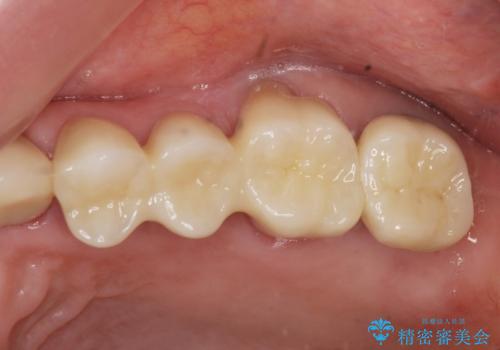

- 61万円(仮歯・フルジルコニアクラウン×4 ・インプラント・チタンカスタムアバットメント )費用は治療当時の料金となります

分岐部病変を併発していた歯は、抜歯としインプラントによる咬合機能の回復。残すことのできる歯は歯周治療後連結補綴を行い歯ぎしりに対抗します。

夜間のナイトガード装着は必須です。